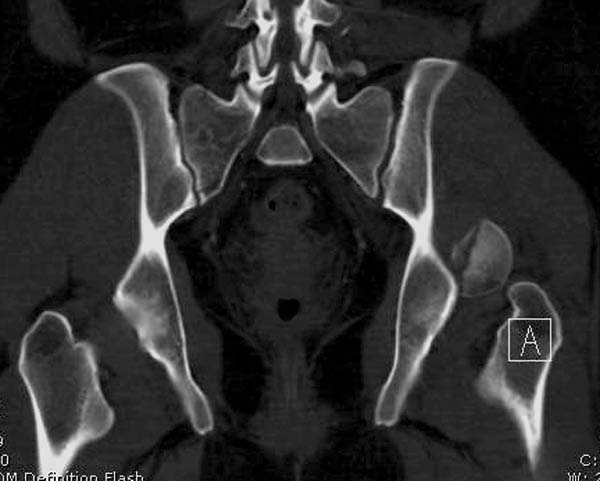

Женщина 28 лет, политравма.

По протоколу обследования больных с травмой сделаны все исследования и выставлен диагноз: разрыв печени и селезенки; множественные переломы ребер и лицевого черепа; стабильный перелом позвоночника, переломо-вывих головки левого бедра, перелом диафиза правого бедра, переломо-вывих правого тарана.